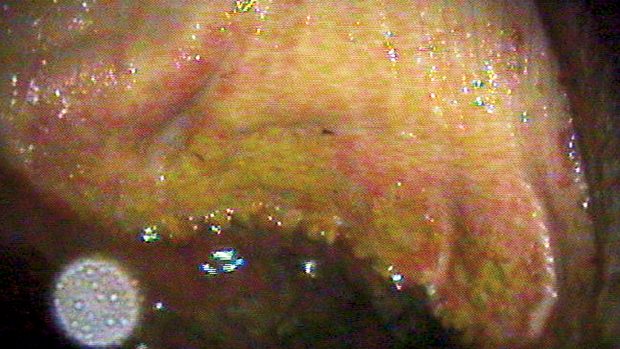

White line disease (seedy toe): what you need to know